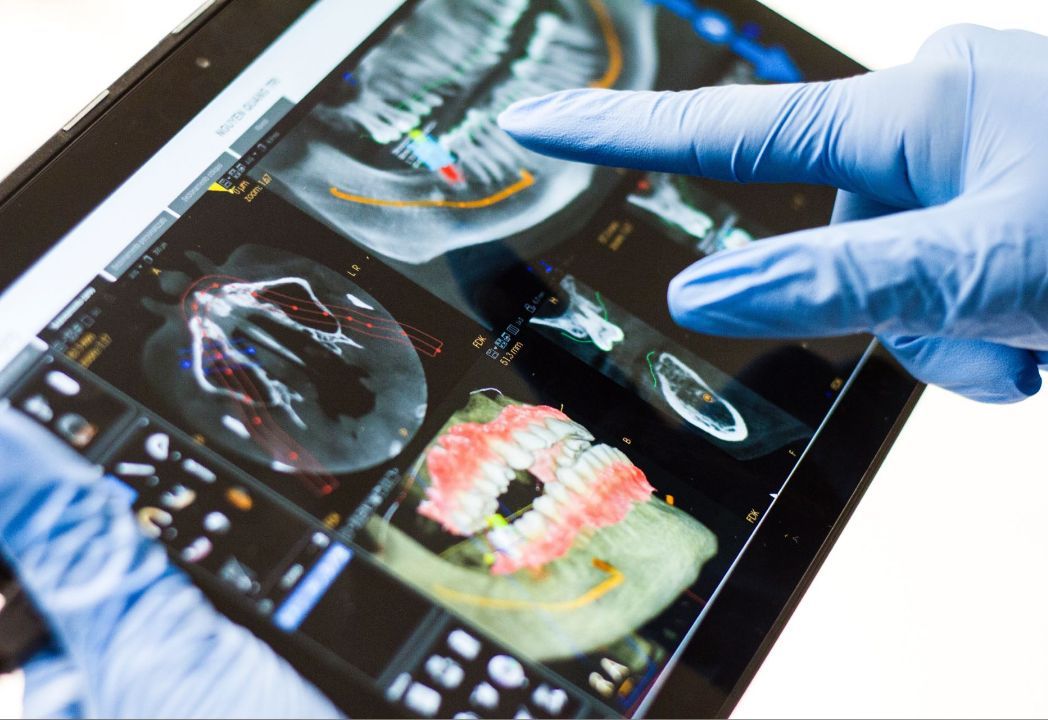

Компьютерная томография зубов - метод стоматологической диагностики, который показывает состояние зубов, корней, челюстной кости и мягких тканей во всех плоскостях.

КТ зубов представляет собой 3D изображение, которое отображается в специальной программе на мониторе компьютера и позволяет рассмотреть состояние челюсти со всех сторон и не упустить ни одной детали.

Зубная диагностика при помощи КТ является абсолютной альтернативой любому другому снимку зубов.

КТ зубов представляет собой 3D изображение, которое отображается в специальной программе на мониторе компьютера и позволяет рассмотреть состояние челюсти со всех сторон и не упустить ни одной детали.

Зубная диагностика при помощи КТ является абсолютной альтернативой любому другому снимку зубов.

Преимущества зубной компьютерной томографии

- Абсолютно точное изображение без искажений

- Возможность рассмотреть необходимой участок со всех сторон

- Быстрое проведение процедуры (не более 1 минуты)

- Минимальная лучевая нагрузка

- Сохранение снимка в электронном виде без риска утраты четкости изображения

Современное оборудование, которое мы используем в семейной стоматологии "Профистиль", обладает минимальной лучевой нагрузкой и совершенно безопасна даже в тех случаях, когда есть необходимость выполнить серию исследований с короткими временными интервалами.

В ПрофиСтиль мы используем аппараты последнего поколения, которые обладают высокими показателями качества изображения и абсолютно безопасны как для взрослых, так и для детей!